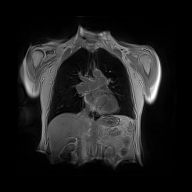

Finally, in Figure 2, we present the deformed image produced by the proposed method on coronal view for a single patient in the two different moments of the respiratory cyrcle. The grids were superimposed on the images, indicating the displacements calculated by the network. The last column shows the difference between the reference and deformed image. One can observe that the majority of the errors occur on the boundaries, as the network fails to capture large local displacements.